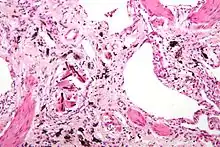

Ferruginous bodies. H&E stain.

They appear as small brown nodules in the septum of the alveolus. Ferruginous bodies are typically indicative of asbestos inhalation (when the presence of asbestos is verified they are called "asbestos bodies"). In this case they are fibers of asbestos coated with an iron-rich material derived from proteins such as ferritin and hemosiderin.[1] Ferruginous bodies are believed to be formed by macrophages that have phagocytosed and attempted to digest the fibers.